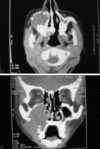

Odontogenic myxoma (OM) is a rare and locally invasive benign neoplasm (comprising of 3-6% of all odontogenic tumors) found exclusively in the jaws. OM commonly occurs in the second and third decades, and the mandible is involved more commonly than the maxilla. The lesion often grows without symptoms and presents as a painless swelling. The radiographic features are variable, and the diagnosis is therefore not easy. This article presents a rare case of OM occurring in the maxilla of a 37-year-old female patient with a brief review of the pathogenesis, clinical, radiological, histopathological, ultrastructural and immunohistochemical characteristics of OM.